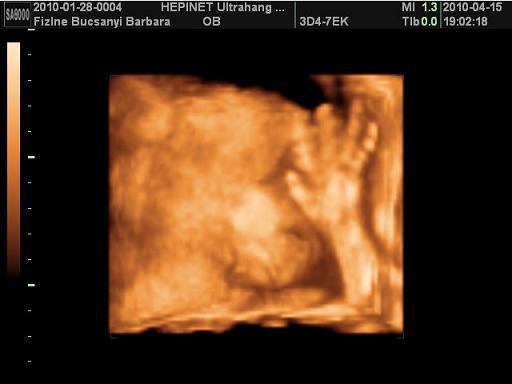

Kép Kép

nagyon klassz az ultrahangos kép, aranyos pofija van Kamillának, és milyen szép nevet választottatok, a második képen, mintha azt mondaná," na most már elég a fotózásból" :-)